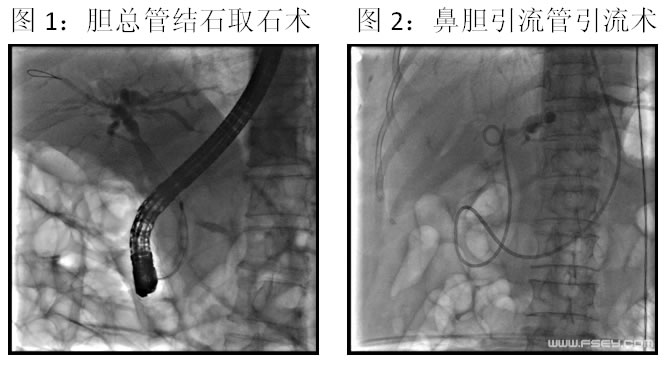

72岁的赵先生因突发上腹疼痛、尿黄2天入住我院消化内科。结合腹部CT、胰腺功能、肝功能等检查,明确诊断为急性胆源性胰腺炎。陈渭副主任医师带领的团队及时为患者进行了ERCP诊疗,造影证实为胆总管结石致胰腺炎,立即在十二指肠镜下给予取出胆总管结石并行鼻胆引流术,术后患者腹痛即明显缓解,第二天黄疸明显消退,恢复进食,现已康复出院。

据消化内科陈渭副主任医师介绍,胆道结石、感染等胆道因素导致的胰腺炎统称胆源性胰腺炎,是我国胰腺炎的主要类型。当胆总管内的结石在胆管出口处嵌顿,将导致胆汁和胰液流出受阻并引起胰腺炎,若梗阻不能及时解除,极易发展至重症胰腺炎并导致全身多脏器损伤、危及生命。首选的治疗是及时取出嵌顿的结石,解除胆总管和胰管的梗阻,ERCP便是针对这种情况的有效微创治疗手段。ERCP是经内镜逆行胰胆管造影的英文缩写,即在十二指肠镜下经十二指肠乳头插管注入造影剂,从而逆行显示胰胆管的造影技术,是目前公认的诊断胰胆管疾病的金标准。因为可进一步行切开、扩张、引流、取石等内镜下治疗操作,ERCP也是胆胰疾病的重要微创治疗手段。

目前我院消化内科已全面开展ERCP诊疗操作,可进行胆管结石、胆管癌等各类胆道疾病的微创诊治,例如内镜下乳头括约肌切开术、内镜下胆管扩张术、内镜下胆管结石取石术、内镜下鼻胆管引流术等,创伤小,恢复快,尤其适合不能耐受或不愿行手术治疗的患者,均取得了较好的疗效。而对于胆管或胰腺肿瘤导致梗阻性黄疸而又失去手术机会或不能耐受手术治疗的患者,可行内镜下胆管支架内引流术,能有效提高生活质量。